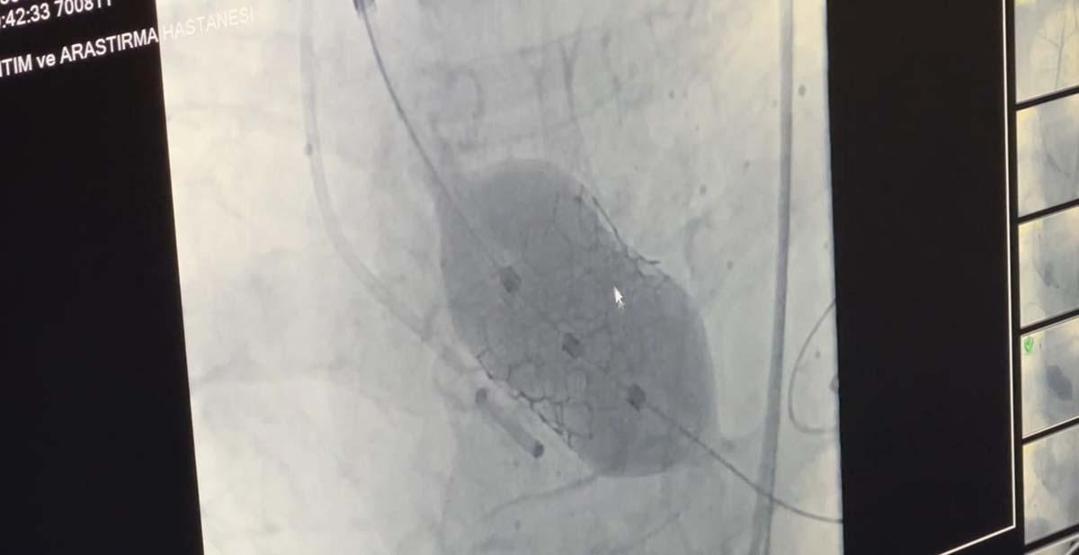

Dünyada 18’nci, Türkiye’de ilk: 4 yaprakçıklı aort kapağına TAVİ operasyonu